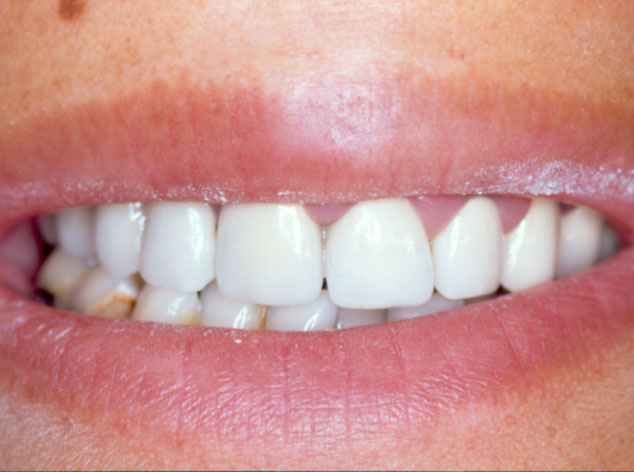

Imagen intraoral del resultado final obtenido después de la cirugía de la osteotomía de Obwegeser, en la que se retruyó la mandíbula aproximadamente tres milímetros; se aprecia la oclusión estable y la corrección de la asimetría que presentaba previamente la paciente.